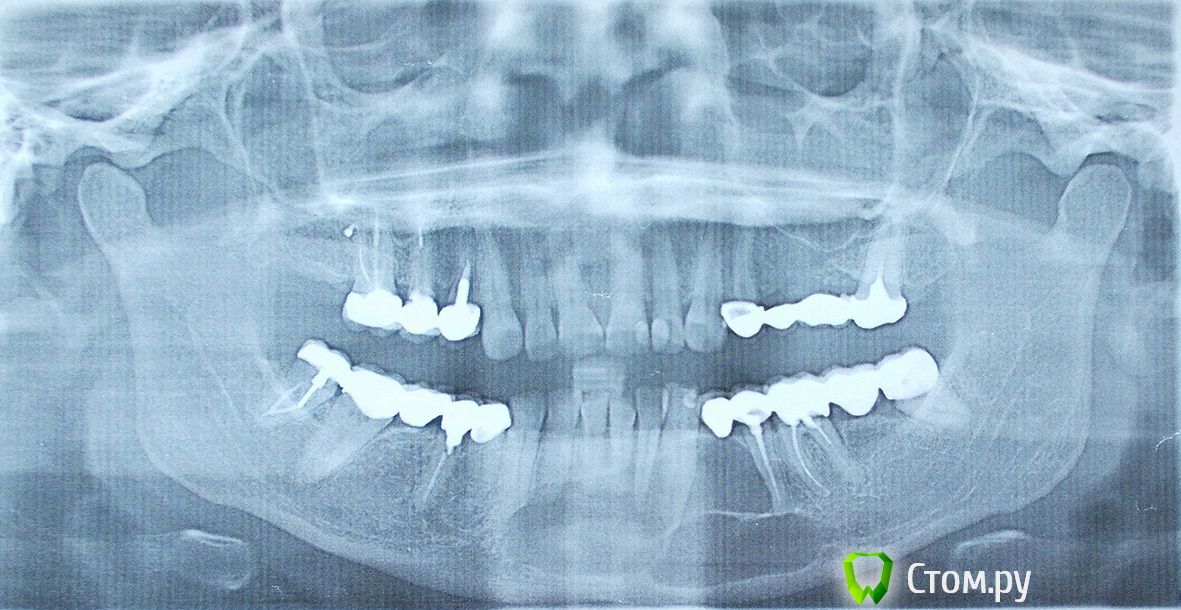

Helenka Опубликовано 21 сентября, 2014 Поделиться Опубликовано 21 сентября, 2014 Добрый день! Помогите пожалуйста найти другой способ лечения, от предложенного мне на днях. История болезни. В сентябре 2006 года была обнаружена киста зуба 4.4. Врачи в городской поликлинике предложили удалить три зуба и операцию в ЧЛХ. Конечно я не согласилась, пошла к частному стоматологу, она предложила лечение. Не могу сейчас описать какое, я не специалист. Мы удалили только один этот зуб и через него закладывали лекарство, в течении полугода это длилось. Сделали контрольный снимок в марте 2007 г. Врач сказал, что все вылечили. После чего я протезировалась. Все эти годы не ходила к врачу, хватило того полугода, да и абсолютно ничего не беспокоило. Недавно она мне позвонила и предложила сделать контрольный снимок. Снимок сделала. Она в ужасе. Отправила в ЧЛХ. Там сказали, что удалить нервы с нижних передних 6 зубов и будут делать операцию. А они у меня здоровые! Прикрепляю все снимки. Может надо вначале пройти какое-нибудь обследование, почему киста такая большая? Может ее уменьшить каким-нибудь лекарством? Есть ли у нас в России клиники занимающиеся лечением таких кист, а не вырезанием половины челюсти? Заранее благодарю за ответы. Ссылка на комментарий

dr-krasnov Опубликовано 21 сентября, 2014 Поделиться Опубликовано 21 сентября, 2014 Киста такая большая, потому что росла 7 лет. Лечением таких больших кист занимаются хирурги, например в НИИ Стоматологии и челюстно-лицевой хирургии в Москве. 2 Ссылка на комментарий